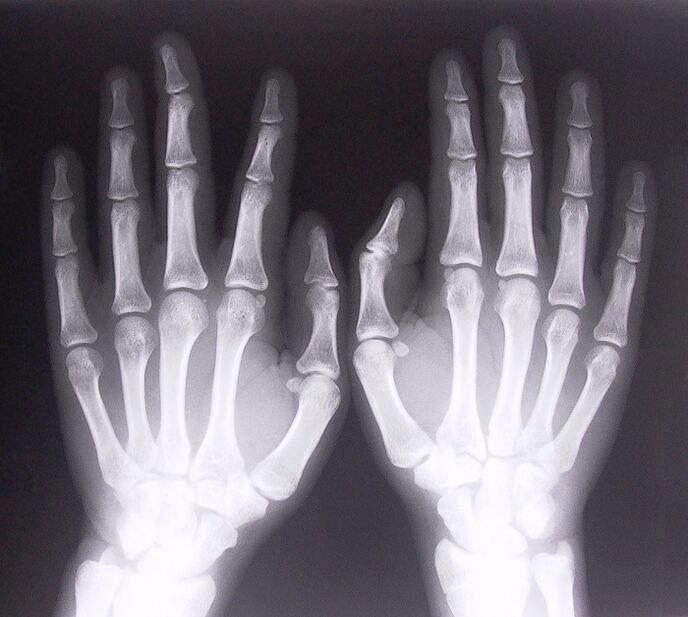

- Stenosing ligamentitis. Don gano dalilin cutar, ya zama dole a yi x-ray. Alamun sun kasance na yau da kullun: motsi mai raɗaɗi na hannu, madaidaicin dabino da aka kama. Hakanan, yayin haɓakawa, yawanci ana jin dannawa.

- Ɗauki x-ray.